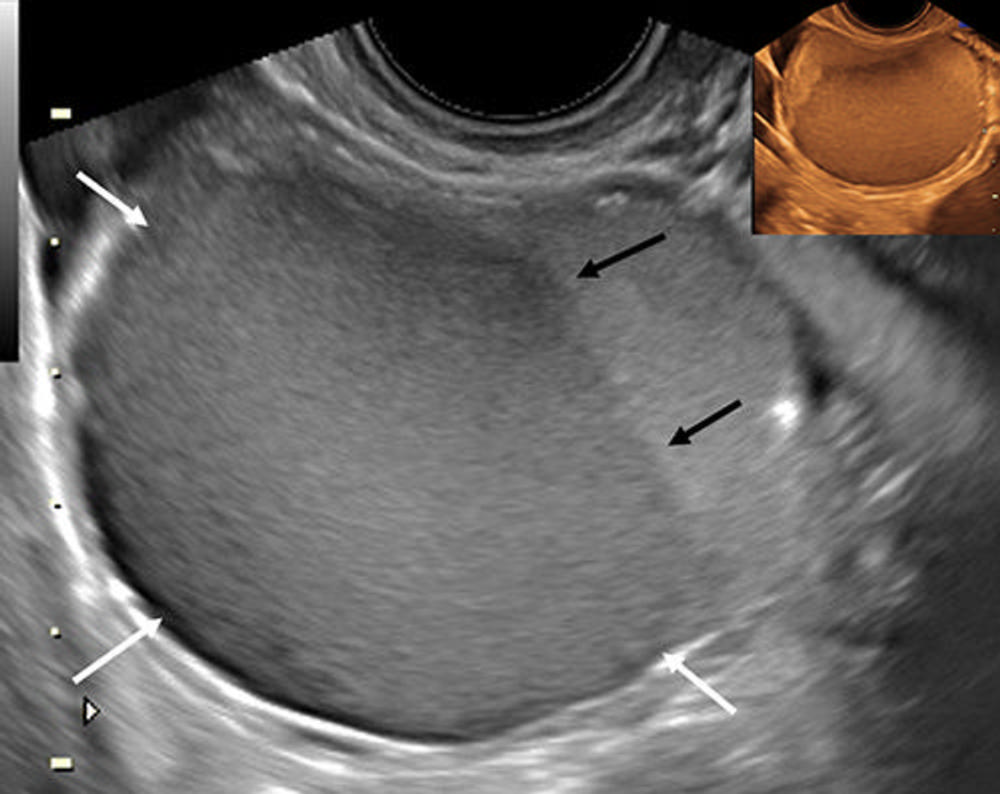

Figure 7. Transvaginal longitudinal US scan in a 31-year-old patient with deep dyspareunia shows an endometrioma with homogeneous low-level (ground glass) echoes (white arrows) and fluid-fluid level (black arrows). Sepia inset in transverse view shows similar observations, a category A (direct endometriosis) observation. Adapted, with permission, from Young SW, Groszmann Y, Dahiya N, et al. “Sonographer-acquired ultrasound protocol for deep endometriosis” Abdominal Radiology.